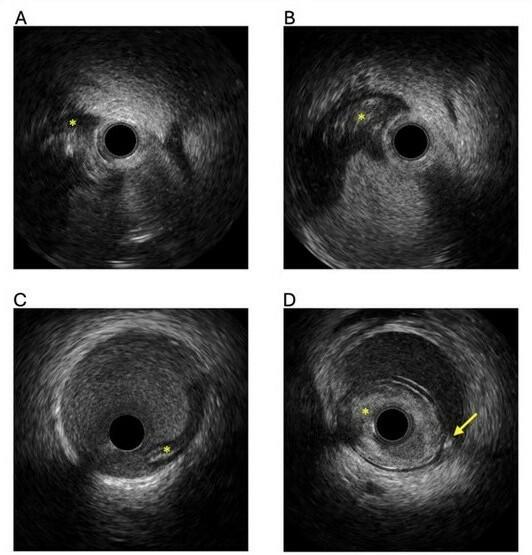

The diagnosis of SCAD is based on clinical presentation and the recognition of well-described patterns seen on coronary angiography. Intravascular imaging (Figure 1) can assist with diagnosis, but carries risk of extending the dissection. With improvement in resolution, coronary computed tomography angiography (CCTA) is increasingly being used, but coronary angiography remains the gold standard for SCAD diagnosis.

5) Intravascular ultrasound (IVUS) should be used (if available) in cases of high-risk SCAD with a Thrombolysis in Myocardial Infarction (TIMI) flow of less than 3. IVUS will confirm the wire position (luminal/non-luminal), assess the extent of the dissection and hematoma, and allow accurate measurement of the vessel size to guide stent selection and balloon sizing (Figure 1). Optical coherence tomography (OCT) provides very helpful high-resolution images of SCAD in ambiguous lesions (Type 3 SCAD) and in distal SCAD with diagnostic uncertainty. Of note, OCT requires contrast injection that may create or propagate the dissection planes in very proximal SCAD with reduced flow. In 1 study of 65 patients with SCAD, 7.9% experienced an angiographic complication with OCT use.17 The optimal mode of intravascular imaging in SCAD has not been defined, but IVUS in high-risk cases (proximal SCAD with no flow) reduces the risk of extension of the dissection plane. Intravascular imaging has vital roles in the management of coronary artery disease and has IA level of evidence for the use in PCI in anatomically complex lesions, bifurcations, and long lesions.18 In CTO PCI, meta-analysis data has demonstrated reduced stent thrombosis with IVUS-guided vs angiographic-guided PCI.19